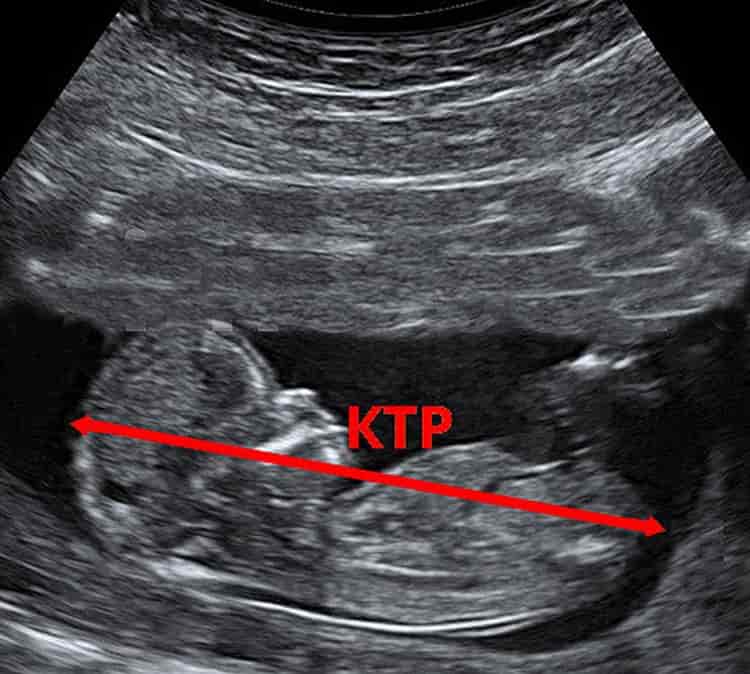

Копчико-теменной размер плода (КТР) – показатель, характеризующий длину сформированного эмбриона. Измеряется в миллиметрах по прямой линии между двумя ориентирами — наружной границей головного конца и копчиком. Длина конечностей плода в этом случае не учитывается. Для надёжности КТР измеряется три раза, после чего за основу берётся минимальное значение. На ранней стадии КТР — основной показатель скорости роста и здоровья плода. Он не зависит от параметров беременной женщины — возраста, национальности, роста и веса. Кроме того, измеряя КТР, специалист может высказаться о сроке беременности с точностью до нескольких дней (обычно плюс-минус три дня). В этом УЗИ значительно превосходит другие методы, в частности, определение дня зачатия по дате начала последнего менструального цикла.

Методика измерения КТР

Существуют сроки беременности, в которые целесообразно измерять именно КТР — с седьмой по четырнадцатую неделю. Ранее специалист идентифицирует эмбрион в матке как округлое образование из одинаковых клеток — плодное яйцо. Позднее четырнадцати недель эмбрион уже настолько развит, что для определения его здоровья используются другие ультразвуковые показатели.

Копчико-теменной размер характеризует скорость роста плода

Степень точности измерения КТР методом ультразвукового исследования велика. Однако необходимо помнить, что на результат в равной степени влияет качество используемой аппаратуры и квалификация специалиста.